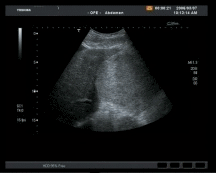

Bei Ultraschalluntersuchungen werden schnell und ungefährlich Informationen über Erkrankungen oder Organveränderungen gewonnen

Abdomensonographie